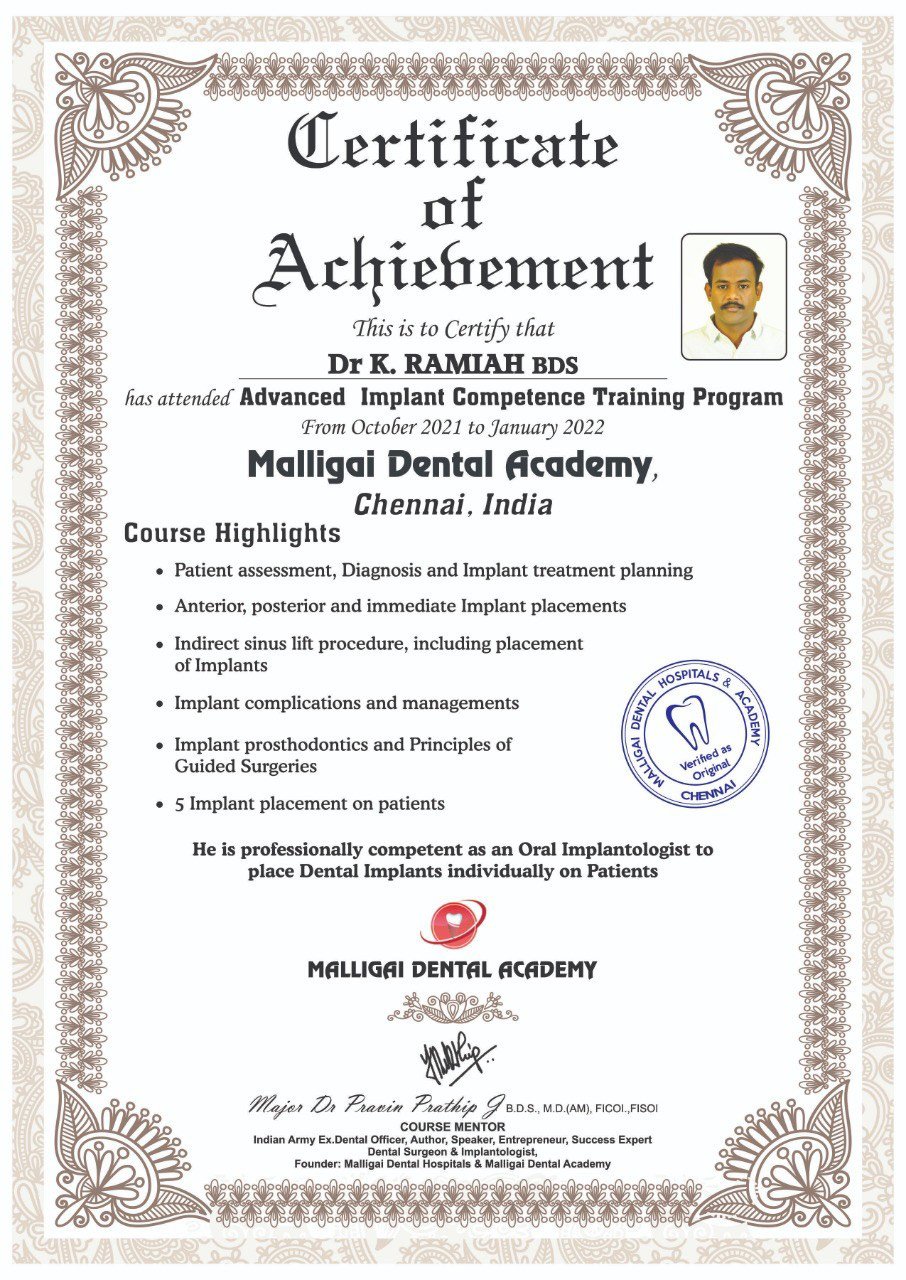

We started our journey in 2021 with a single dental chair and a strong commitment to providing quality dental care. With over 5 years of professional experience, our practice has grown steadily and now operates with three fully equipped dental chairs to serve our patients better. Having completed an MS in Italy, we bring advanced knowledge and global expertise to our treatments, with a special focus on implantology. Over the years, we have successfully handled more than 30,000 consultations and built a community of over 3,000 happy clients, reflecting our dedication to excellence, precision, and patient satisfaction.

Advanced credentials and clinical recognitions